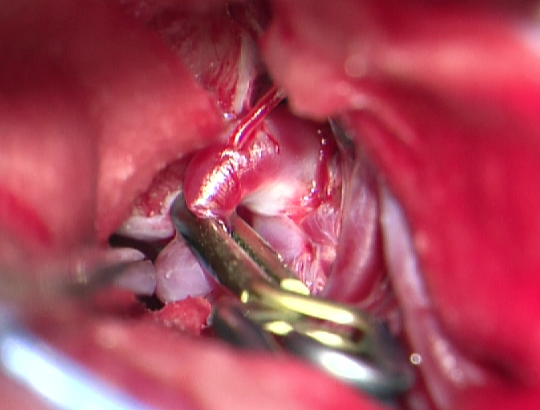

3.开颅手术切除畸形血管团

考虑到患者术前癫痫,且介入术中患者拔管困难,予以行开颅手术切除畸形血管团,并拔出微导管。术中可见微导管及注射的Onyx胶(血管内黄色部分及黑色部分),游离血管后近端用临时阻断夹阻断,远端剪断,打开临时阻断夹将微导管自股动脉鞘拔出,然后切除畸形团。术后复查头颅CT提示钙化及介入术中胶均已切除。